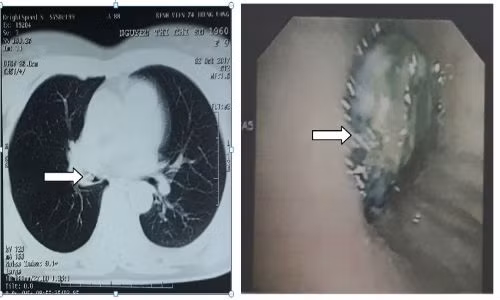

| Hình ảnh CLVT nghi dị vật phế quản phải (hướng mũi tên ảnh trái) và hình ảnh dị vật ở phế quản trung gian phải trên nội soi phế quản ống mềm (ảnh phải). |